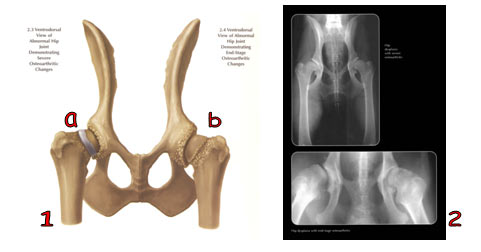

1a. Gambaran ventrodorsal persendian pinggul normal.

1b. Gambaran ventrodorsal persendian pinggul yang menderita luksasi caput femoralis.

2. Gambaran radiologi ventrodorsal gambar 1.